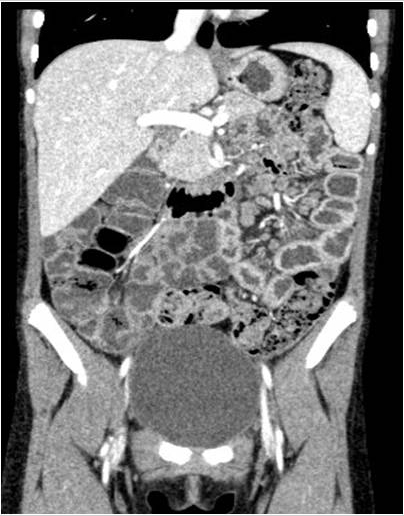

Se aprecian cuatro lesiones hipodensas en el bazo. En los cortes coronales se aprecia hipercaptación mucosa en las asas del yeyuno, adenopatías de tamaño patológico, aumento de la vascularización del meso y líquido libre en la fosa iliaca derecha.

• Hipercaptación mucosa en las asas del yeyuno, con adenopatías regionales de tamaño patológico y aumento de vascularización en el meso.

• Se observan al menos cuatro lesiones focales esplénicas, hipodensas y mal definidas, con bazo de tamaño normal.

• Discreta cantidad de líquido libre en fosa iliaca derecha.

Estos hallazgos en conjunto sugieren un proceso inflamatorio de tipo infeccioso, ya que no existe un engrosamiento de las paredes de las asas del yeyuno que sugieran una etiología neoplásica (linfoma o tumor carcinoide), aunque esto no puede descartarse con seguridad.